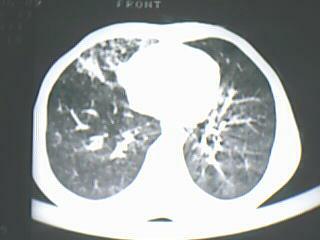

以下是引用随光逐影在2009-8-7 15:40:00的发言:[br]考虑右肺继发性肺结核并右肺上叶空洞形成,两肺支气管播散;不排除右肺上叶空洞内霉菌感染可能。

以下是引用jiangjing在2009-8-7 14:38:00的发言:[br]右上肺张力空洞,酐珞坏死灶,支气管扩张,多发播散灶,纵膈淋巴结显示,胸膜增厚---结核